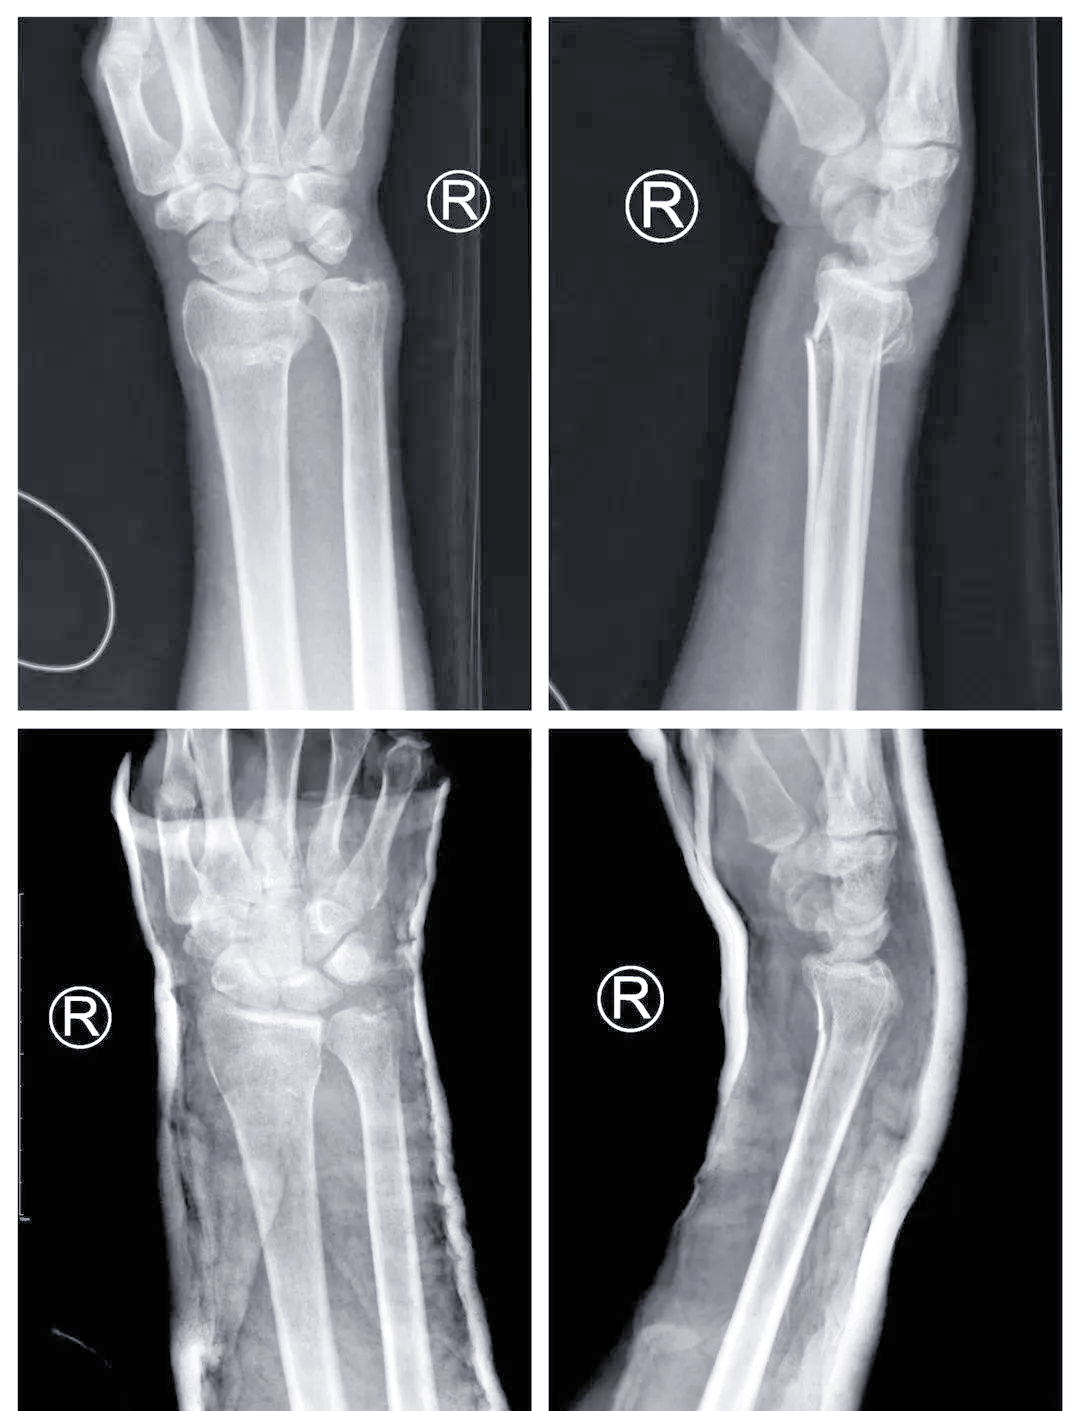

骨折的三大特征分别是畸形骨擦音及骨擦感异常活动,以下是对这三大特征的详细解释畸形由于骨折是身体的支撑结构,骨折时,骨骼的连续性或完整性中断,导致骨折部位出现明显的形态改变或错位,这种形态上的异常即为畸形骨擦音及骨擦感骨折后,骨折断端之间会相互摩擦,这种摩擦可能会产生声音。

骨折的三大特征分别是畸形骨擦音骨擦感异常活动畸形,由于骨折是身体的支撑结构,所以骨折的时候会出现畸形骨擦音骨擦感,骨折后,骨折断端之间摩擦导致的声音或者是一种感觉异常活动,是区别于关节的,在关节之外出现的反折活动,这就是骨折的三大特征如果出现这三大特征中其中的一个。